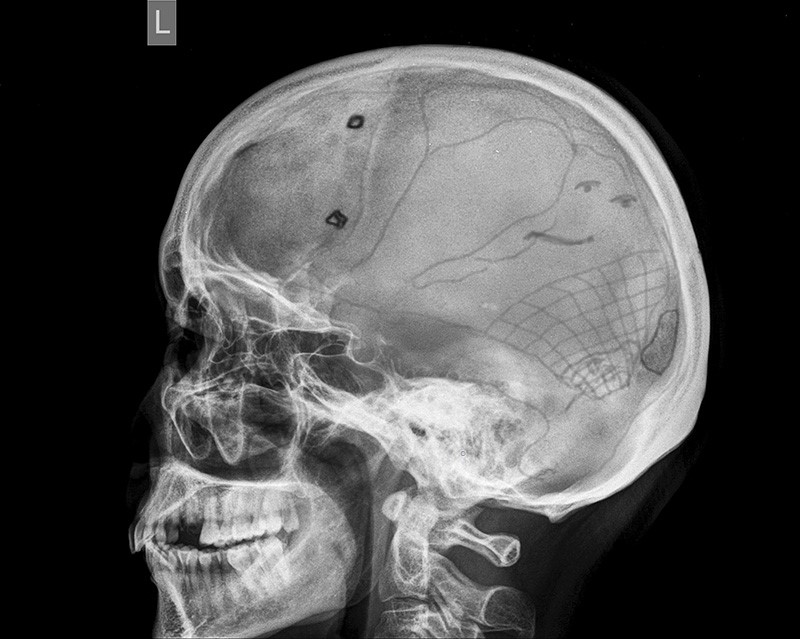

Анатомия детского черепа: Рентгеновские снимки и описание